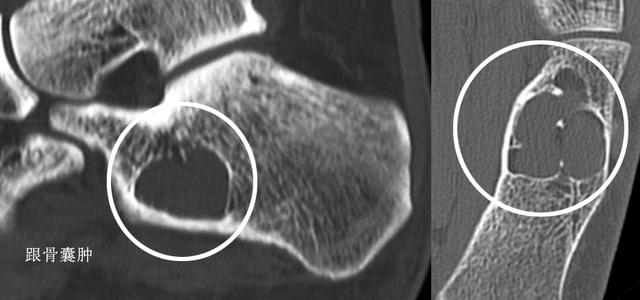

跟骨囊肿诱发的跟痛

说到这个疾病谢医生是感到非常愧疚的,因为在这个疾病上吃过亏。

十余年前有一个朋友的孩子因为跟痛找到了我,当时经验还是比较浅薄,查体之后简单判断了是因为跑跳诱发的跟腱炎,未给与重视。后来一周后疼痛加重,检查X光才发现是跟骨囊肿,还好并未影响孩子的治疗,否则后果不敢想象。

所谓吃一堑长一智,也是从那以后我都会建议跟痛的患者做一个X光检查, 排除囊肿和骨破坏的可能。

小的囊肿一般不会有任何症状,但是如果囊肿较大,产生了疼痛症状,建议手术切除囊肿给与植骨的手术治疗,否则随时有跟骨骨折的风险。